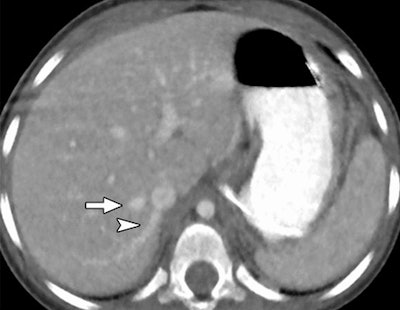

In an objective evaluation, reduced-dose MBIR images had decreased image noise compared with standard-dose 30% ASIR images (for example, 12.7 HU versus 19.4 HU in the aorta, respectively, and 8.7 HU versus 14.2 HU in the liver).

The MBIR images also had less noise (p > 0.004), and spatial resolution was superior overall for MBIR. The readers found MBIR images equivalent to standard-dose images for the lungs and soft tissues (p > 0.05) but inferior for bone imaging (p = 0.004), the group reported.

Image quality was also judged to be sharper with MBIR. Using the same reduced-dose acquisition, lesion detectability was better (32 of 84 rated lesions, 38%) or the same (52 of 84 rated lesions, 62%) with MBIR compared to 100% ASIR reconstruction.